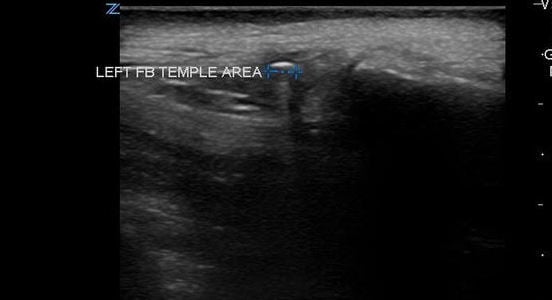

- Foreign bodies will usually appear hyperechoic to the surrounding soft tissue.

- Material such as wood, glass, and plastic tends to produce shadowing (Videos 2-4 and Figure 2) which will be visualized in the tissue deep to the foreign body.

- The area is scanned throughout its entirety in search for a hyperechoic object in both the sagittal and transverse planes as it can sometimes be much easier to visualize an object in one plane but not the other. Be aware of possible surrounding tissue inflammation or abscess.

- Visualization of foreign bodies is easiest when the probe is parallel to the object and therefore attempts should be made to visualize the area in question from many angles if possible.

- Once a foreign body is localized, the depth from the skin can be measured as well as the size of the object.

- Survey the area surrounding the object for vessels. Vessels in close proximity to the object may prompt the practitioner to avoid probing the area.